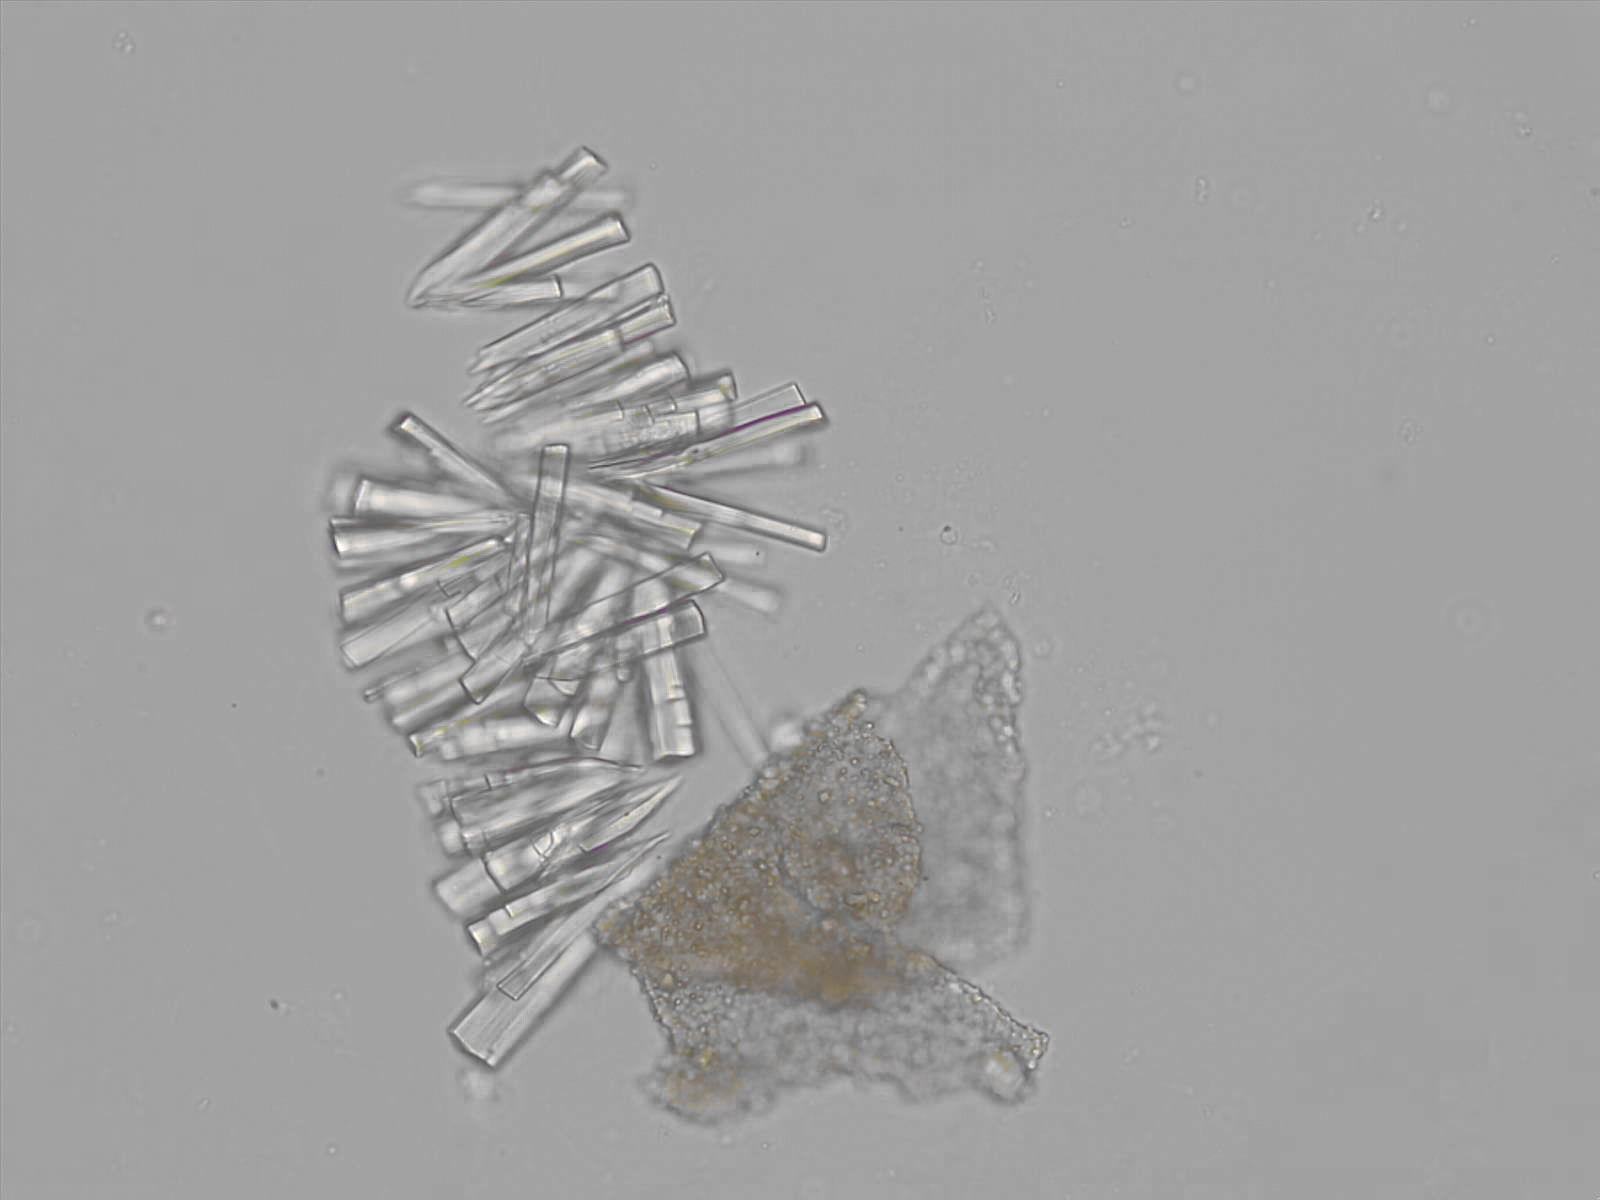

Calcium phosphate - Wedge form

Synonyms: Brushite, CaHPO₄·2H₂O

Calcium phosphate crystals frequently occur in normal urine with an alkaline pH (>7.0), but are also seen in people who form kidney stones. They are colorless and show great morphological variation. The crystals may occur as prismatic shapes, needle or wedge-shaped rods with usually blunt ends, and sometimes as star-shaped clusters (rosettes). These shapes are usually strongly birefringent. In addition, large, flat plates with irregular edges and granular structure can also be found. However, these plates are not birefringent.

Wedge-shaped calcium phosphate crystals may resemble crystals of uric acid, but the distinction can be made on the basis of the urinary pH (acidic in uric acid, basic in calcium phosphate) and the optical behavior under polarized light: uric acid crystals are birefringent, calcium phosphate sheets usually are not.